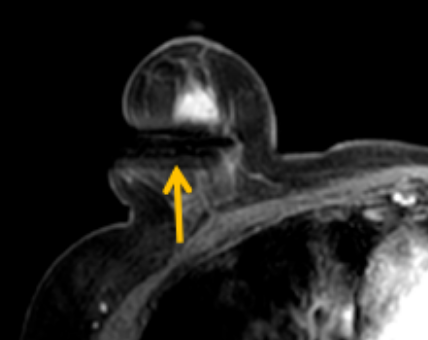

陳寶瑩評估圖像后發(fā)現(xiàn)病變?yōu)閮H僅在磁共振增強時顯示,為非腫塊樣病變,比較散,必須取得足夠多的組織才能確保病理檢查的準(zhǔn)確性,常用的核芯針活檢獲取的組織較少,因此最終確定了磁共振引導(dǎo)下行真空輔助抽吸旋切活檢。取得患者及家屬認(rèn)可后,陳寶瑩帶領(lǐng)團(tuán)隊開始進(jìn)行術(shù)前準(zhǔn)備。

針對患者乳房小固定難度大這一問題,陳寶瑩通過巧妙體位和固定器的調(diào)整,順利固定好乳房。經(jīng)過磁共振多模態(tài)掃描,陳寶瑩找出病變活性成分相對集中區(qū)域,精準(zhǔn)確定穿刺路徑,置入引導(dǎo)針、旋切針,到位后多角度旋切取出足量組織,拔除旋切針后即時行磁共振掃描,精準(zhǔn)取得組織且術(shù)區(qū)出血很少,遂加壓包扎,整個過程非常順利,旋切活檢后患者回家休息。兩天后隨訪,李女士沒有任何不適,五天后皮膚上幾毫米的小切口已經(jīng)愈合。最終病理結(jié)果證實為乳腺導(dǎo)管原位癌,為早期乳腺癌,為患者后續(xù)針對性治療奠定了基礎(chǔ)。